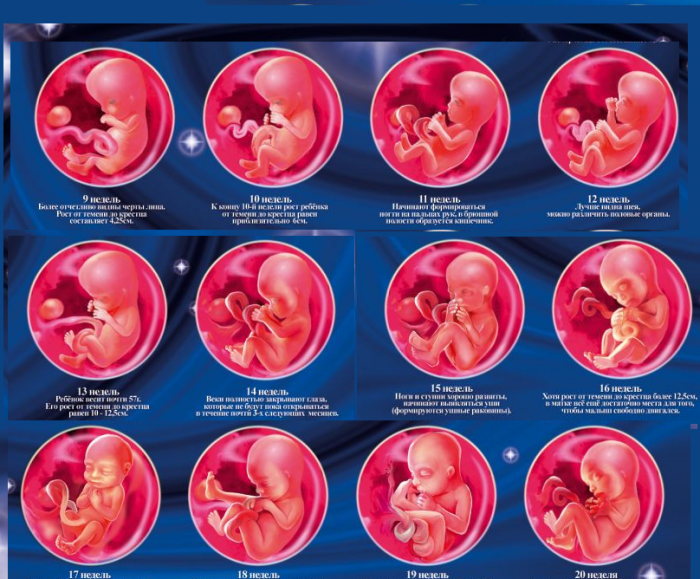

Формирование Плода в Первом Триместре: Важные Этапы